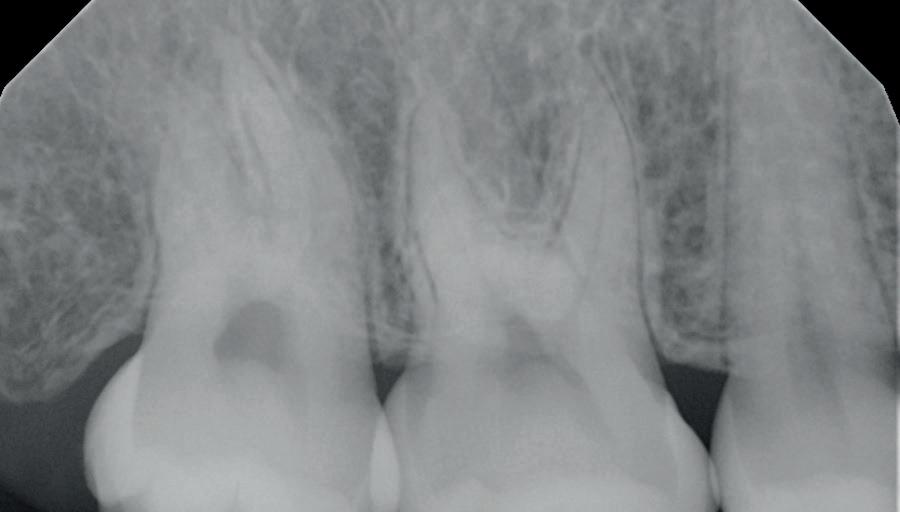

și „punte cu trei unități”, în prezent fiind la egalitate cu majoritatea sistemelor de titan. Deși datele pe termen lung nu au confirmat încă aceste rezultate bune, succesul de până acum este încurajator, astfel încât clinicienii profită de beneficiile clinice ale dioxidului de zirconiu în practica zilnică, introducând implanturile ceramice ca opțiune suplimentară în spectrul de opțiuni alături de cele de titan (fig. 1). Chiar

Figurile:

1. Implanturi din titan (stânga) și zirconiu (dreapta). 2. Recesii la implanturile ceramice (stânga) și din titan (dreapta). 3. Țesut moale cu implant din zirconia, lipsit de inflamație.